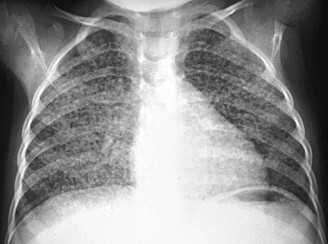

TB-Lunge mit Knötchen, Röntgenfoto

TB-Lunge mit Knötchen, Röntgenfoto [1]

Im Römischen Reich schreibt Hyppokrates über TB, hält dabei aber die Knötchen für die Ursache. Dabei sind die Knötchen die Folge. Hyppokrates erkennt den Infektionsweg nicht (S.39). Es sind gelblich-graue, hirsekorngrosse Flecken [an der Lunge] (S.40).